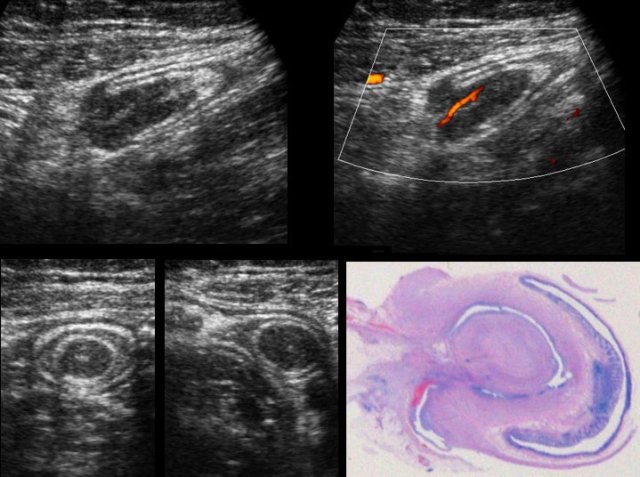

DIE implants on the outer surface of the colon in four different patients.

DIE implants (*) in Douglas pouch, are asymmetrically localized, solid, hypoechoic, poorly vascularized masses, which are continuous with the outer hypoechoic muscularis layer of the colon.

The overlying hyperechoic submucosa,  and also the colonic mucosa are generally intact. This explains also why blood in the stool is quite rare in DIE.

The outer contour of these hypoechoic masses is mostly firmly adherent to uterus and/or cervix. Often there is spiculation or “tethering” visible on the outer margins.

TVUS image of DIE with operative specimen.

In this patient, the hyperechoic submucosa of the ventral sigmoid wall, clearly overlies the large DIE implant (*). Note also the completely normal dorsal sigmoid wall.

The resected specimen shows that the (sub)mucosa (arrows) is intact and overlies the DIE (*). As expected, also this patient had no history of rectal bloodloss.